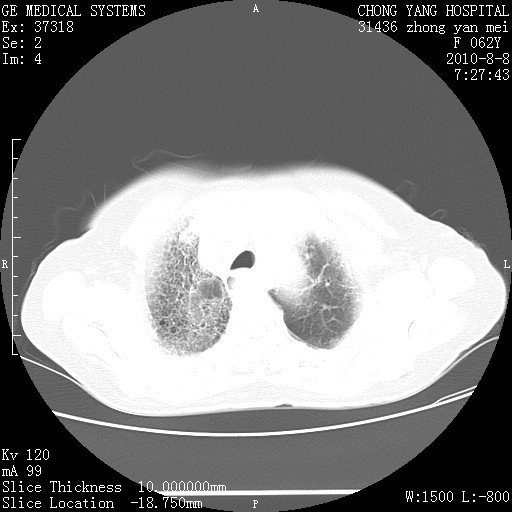

标题: CT28269:F62Y咳嗽胸痛数月。 [打印本页]

标题: CT28269:F62Y咳嗽胸痛数月。

两肺弥漫性间质纤维化伴继发性支扩。

考虑特发性肺间质纤维化

考虑两肺间质性肺炎并肺间质纤维化。

双肺间质纤维化合并感染、肺气肿

双肺间质纤维化

1.肺间质纤维化.

2.纵隔淋巴结肿大。

3.迷走右锁骨下动脉。

两肺间质改变,纵隔淋巴结肿大,需要考虑结节病的可能。